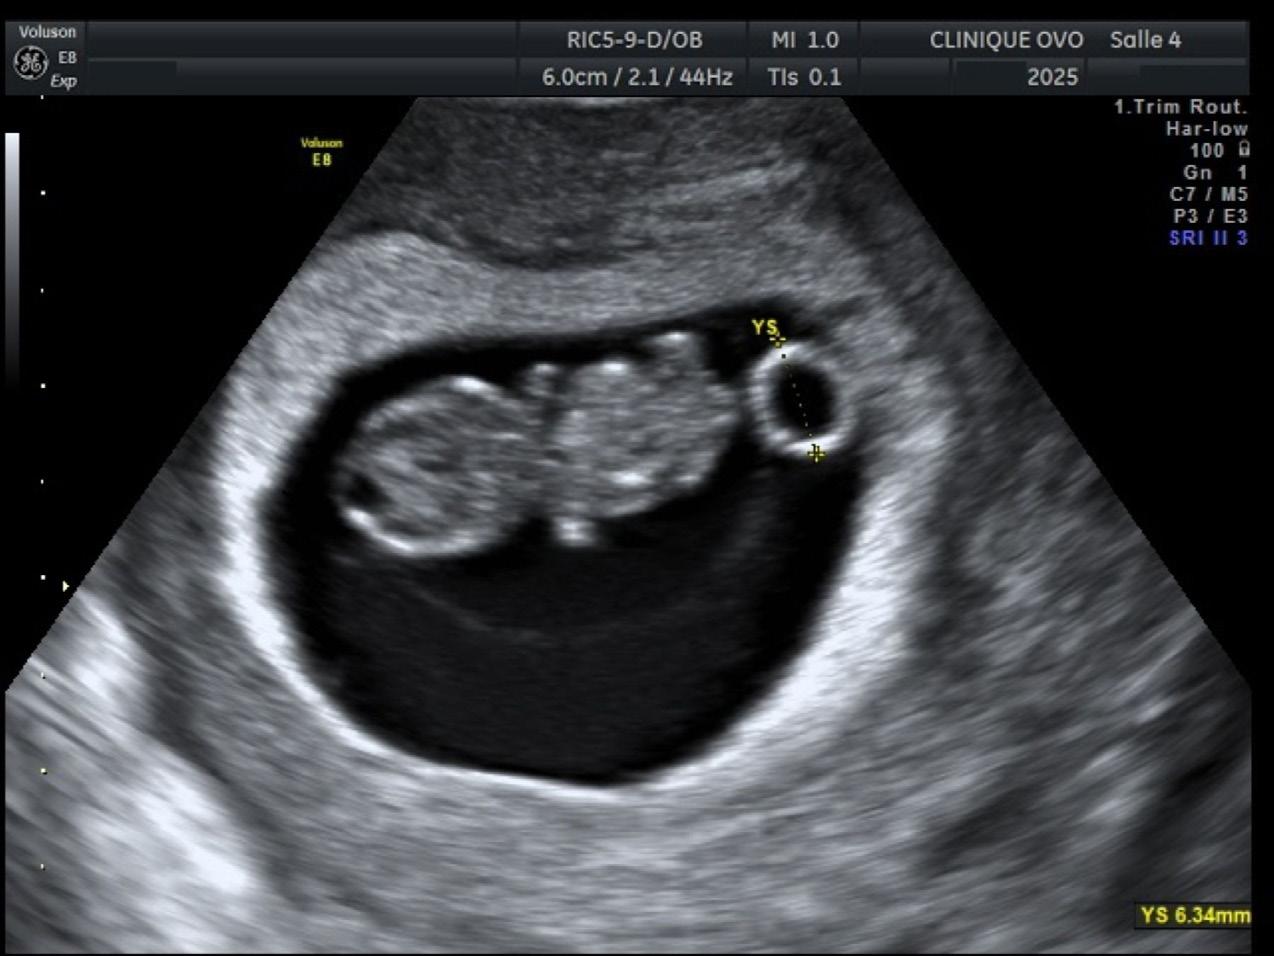

simplement ne pas y avoir de grossesse. Pendant l’échographie, on mesure la longueur de l’embryon, de la tête (rhombencéphale) à la pointe de la colonne ainsi que le sac vitellin (là où se nourrit l’embryon) (Figure 3). De plus, on fait un tracé de l’activité cardiaque en mode « M ». Selon les recommandations de la Fetal Medicine Foundation (FMF), on n’utilise pas le mode pulsé avant huit semaines de grossesse, parce l’embryon est encore en train de former ses organes2. On veut alors éviter d’accroître la chaleur des tissus à ce stade critique.

L’échographie de viabilité

Son objectif est de démontrer qu’il y a une grossesse à l’intérieur de l’utérus. L’embryon doit avoir une activité cardiaque, et sa taille

doit concorder avec la date de conception. Malheureusement, la grossesse peut se retrouver à l’extérieur de l’utérus (non viable et dangereuse pour la patiente), il peut y avoir une grossesse arrêtée ou